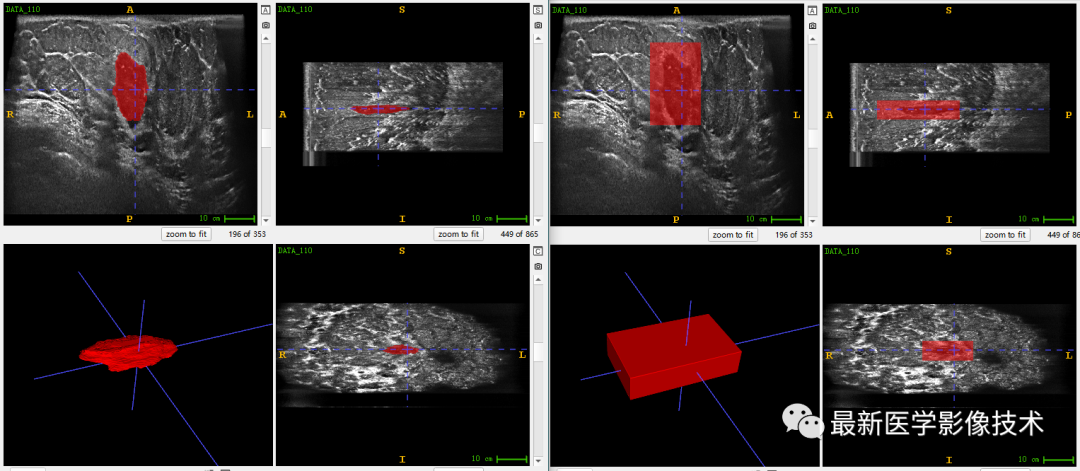

乳腺肿瘤分割采用两阶段分割网络,第一个网络进行粗分割定位肿瘤位置,第二个网络进行精分割得到肿瘤精确轮廓,然后在根据精分割mask和对应ROI图像进行良恶性分类。具体实现可以参考这篇文章TDSC-ABUS2023——2023 年自动化 3D 乳腺超声 (ABUS) 的肿瘤检测、分割和分类挑战.

验证集分割和检测部分结果如下所示。